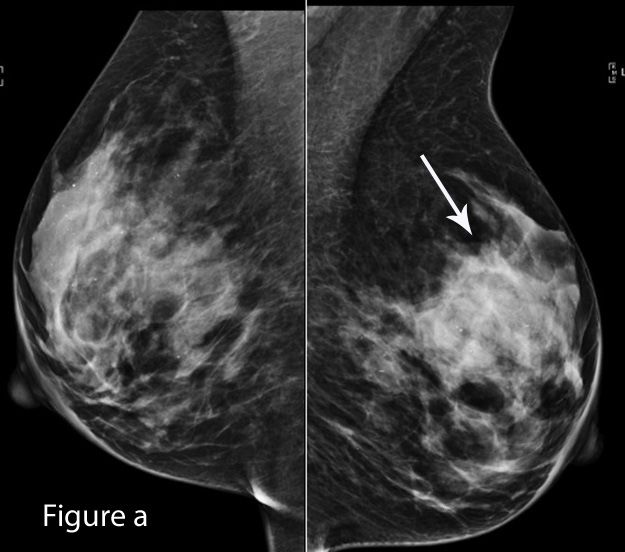

Screening with tomosynthesis in conjunction with digital mammography lowers recall rates and increases cancer detection.

Lower recall rates, more cancer detection were seen with 3D digital breast tomosynthesis, compared with 2D digital mammography.